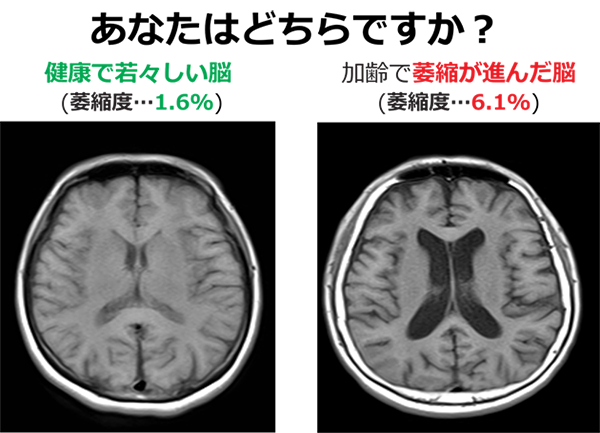

その劣化の指標とされるのが脳の萎縮と白質病変(血管の変化)と言われる変化です。これらは認知症のリスク因子の一つとして知られています。

人は歳をとることに伴い、老眼になったり、白髪や皺が増えるなど、自他ともに顕著に分かる老化を経験しますが、それと同じように、脳も加齢に伴い変化します(加齢性変化)。そして、その進み方の度合いは脳の「萎縮」と「血管の変化(白質病変)」によって把握することが可能です。

最も重要な事実として知るべきなのは、この進行速度には大きな個人差があるということです。誰でも脳の変化は30代から始まり、40~50代の頃には、大きな差が出てきます。